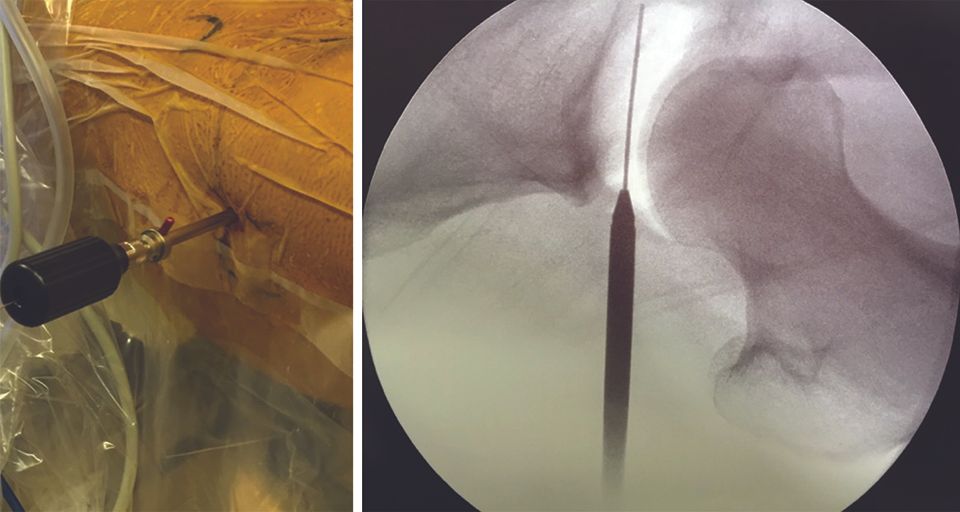

This technique, coupled with general anaesthesia and a neuromuscular blocker to aid the relaxation of the anterior iliofemoral ligament, allows a reduction in traction force (joint separation) from 500 N to 230–300 N (38,39), thus reducing the risks of potential complications (see “Complications”, above). Next, the nitinol guide is inserted into the spinal needle (Fig. 4). After withdrawing the spinal needle, the hollow trocar is introduced on the nitinol guide (Fig. 5) and the arthroscope is inserted. The arthroscopic view is shown in Figure 6.

The nitinol guide is introduced into the spinal needle, then the switching stick is inserted, and then the Half Pipe so as not to lose the portal (Fig. 8). Finally, the different instruments such as the spacer and electric lancet can be inserted.